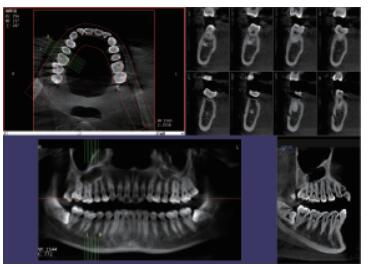

高清晰成像口腔CBCT 牙科CT產(chǎn)品說(shuō)明:

你知道口腔CBCT是什么意思嗎?口腔CBCT是一類特殊的CT,其工作原理是通過(guò)X線發(fā)生器以較低的射線量發(fā)射錐形X束,圍繞投照體做環(huán)形數(shù)字式投照,將圍繞投照體多次產(chǎn)生的二維投射影像通過(guò)圖像重建算法獲得三維圖像。成像效果更好,有助于醫(yī)生的診斷,對(duì)于種植、綜合診斷、正畸等牙科診斷均有較大幫助。

在口腔影像等細(xì)分領(lǐng)域,口腔CBCT的成像質(zhì)量?jī)?yōu)于CT和普放。CBCT的X線利用率更高,且生成的圖像具備很高的各項(xiàng)同性空間分辨率。CBCT技術(shù)優(yōu)勢(shì)如下:

三維重建任意斷層

專有三維重建算法,可提供任意位置高清斷層影像。

高清口腔全景影像

通過(guò)三維容積影像,提取高清口腔全景影像。

多平面組合重建

可同時(shí)觀察軸向面、冠狀面和矢狀面圖像,方便臨床診斷。